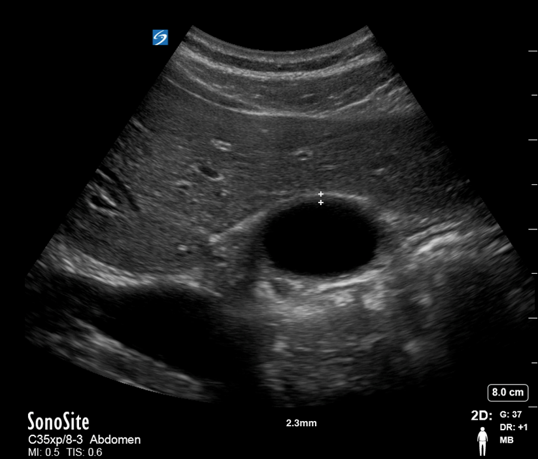

Gallbladder Normal Wall Measurement - Transverse Image